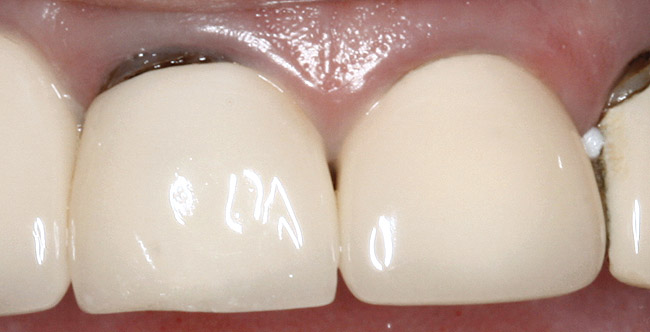

Figure 14  ENDODONTIC AND ESTHETIC PARAMETERS The previous restorations have a height-to-width ratio < 100%.

Figure 14

Figure 15 ENDODONTIC AND ESTHETIC PARAMETERS  The same teeth after crown lengthening and a new restoration created a more esthetically pleasing 80% height-to-width ratio.

Figure 15